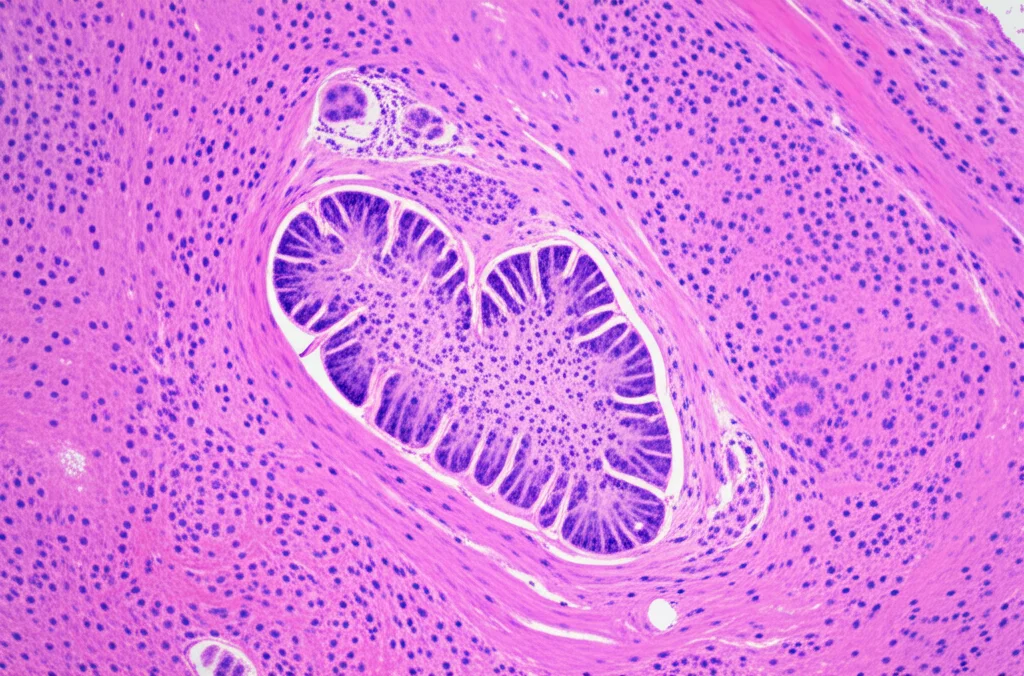

Partiamo dalle basi. Gli rNETs sono lesioni piuttosto rare che si sviluppano nello strato sottomucoso della parete rettale. Anche se rari, la loro incidenza sta aumentando a livello globale. La cosa importante da sapere è che, nonostante spesso siano piccoli, hanno un potenziale metastatico, cioè possono diffondersi ad altre parti del corpo. Le linee guida attuali suggeriscono che le lesioni sotto i 20 mm possono essere trattate con diverse tecniche, tra cui la TEM, la dissezione sottomucosa endoscopica (ESD) o la resezione mucosa endoscopica (EMR).

Ed è qui che la TEM gioca un ruolo fondamentale. Descritta per la prima volta da Buess, è una procedura chirurgica che richiede una curva di apprendimento significativa. Si utilizzano strumenti simili a quelli della laparoscopia, ma introdotti attraverso l’ano. Il grande vantaggio? Permette una resezione a tutto spessore della parete rettale, rimuovendo completamente la lesione o la cicatrice residua dopo una precedente resezione endoscopica incompleta. Quest’ultima applicazione viene definita “terapia di salvataggio” (salvage therapy). Nel nostro studio, abbiamo voluto proprio confrontare i risultati ottenuti usando la TEM come trattamento primario rispetto a quando l’abbiamo usata come terapia di salvataggio.